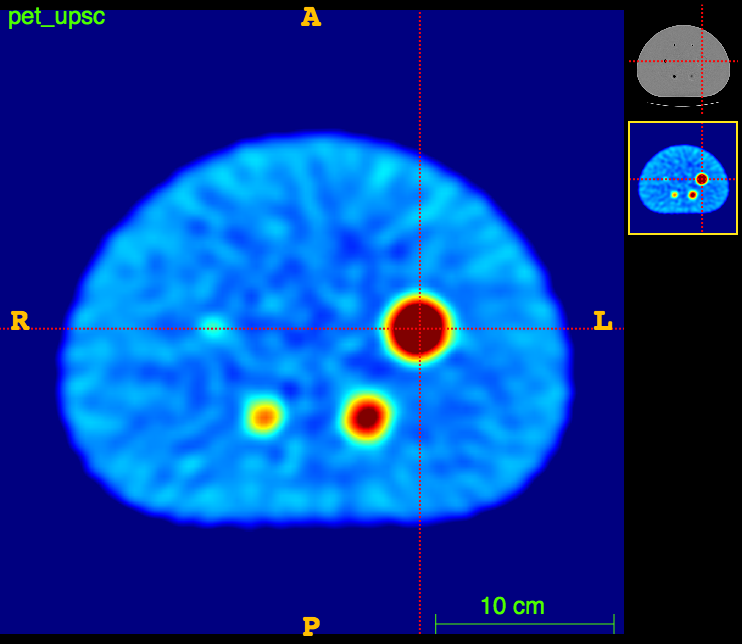

In vitro validation:

The RIDER PET/CT phantom images is a dataset of repeated scans of a dummy (20 scans of the same phantom).

Axial

Sagittal

CT

CT segm.

PET